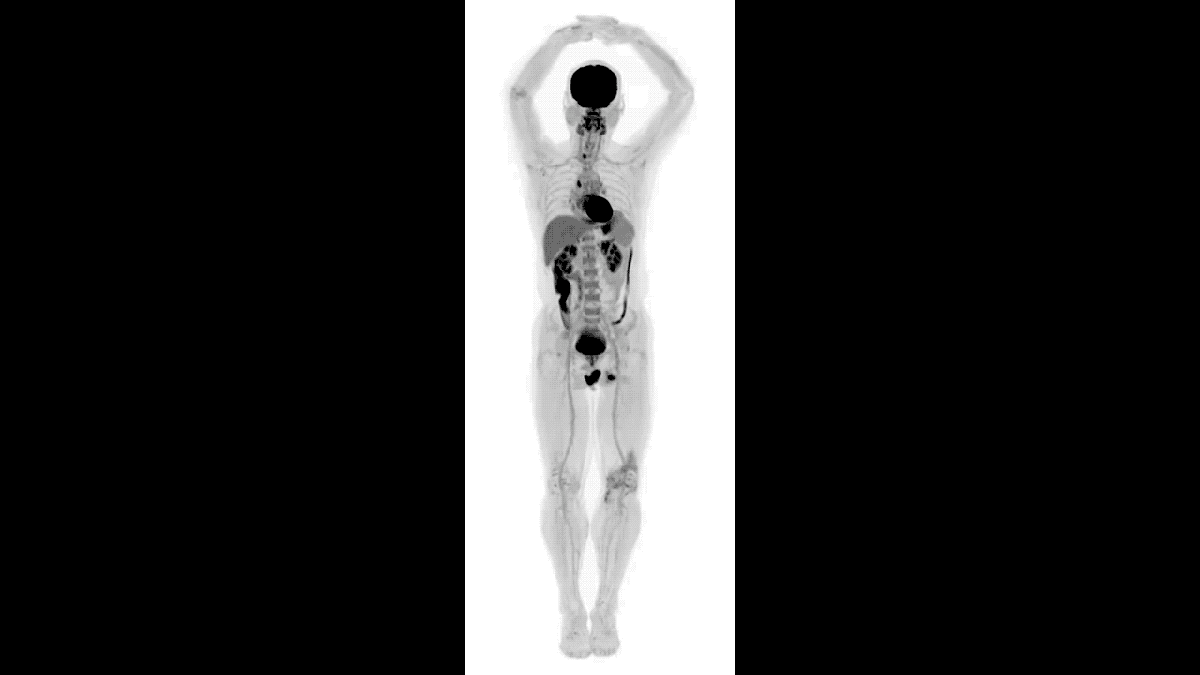

What do you get if you combine the technologies on which the two most successful medical imaging devices — positron emission tomography (PET) and x-ray computed tomography (CT) — are based? You get EXPLORER, the stunning new scanner that can capture an amazingly detailed 3D image of the entire human body in 20–30 seconds.

EXPLORER’s super-fast capture rate — it can scan a body region in about a second — also allows it to take movies of specially-tagged medications and radiotracers as they make their way through a body.

EXPLORER is 40 times as fast as a PET scanner, making it more feasible to do repeated studies on an individual, and, of course, there are the movies that can provide an unprecedented look at the in-body progress of radiotraceable agents. EXPLORER’S also 40 times more sensitive than PET scanners, so it will cause patients to be exposed to far less radiation during diagnosis than traditional PET or CT scans.